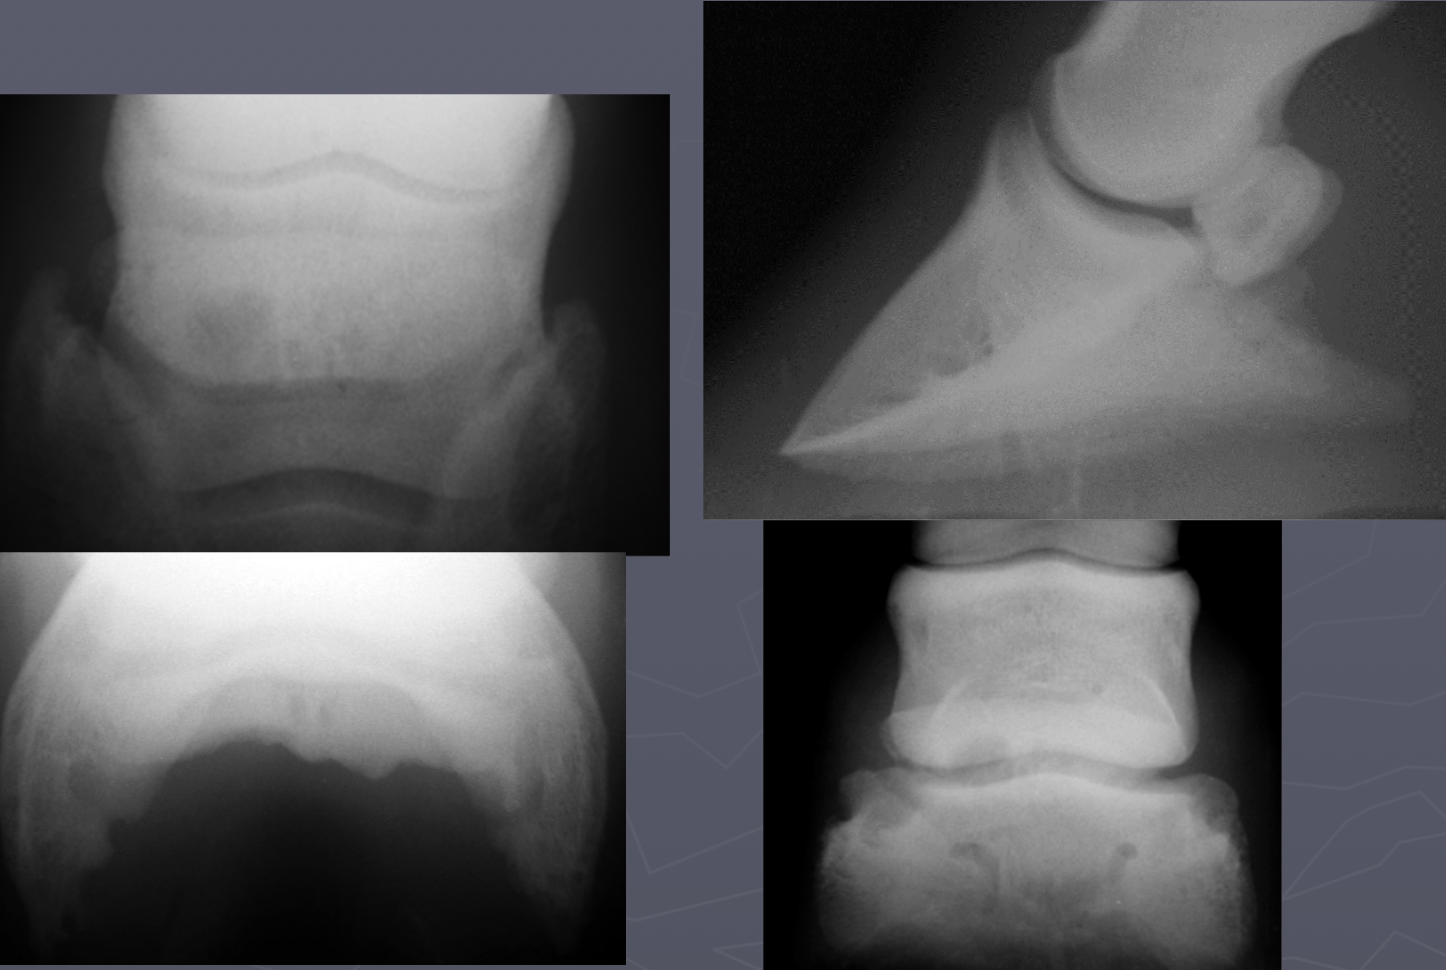

which OCD lesions are these in the dog

A = cd humerus

B = medial humeral condyle (elbow)

C = medial trochlear ridge (ankle)

D =lateral femoral condyle (knee)